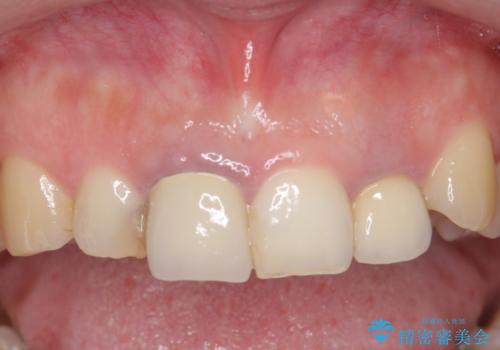

- 前歯の色や長さ、歯茎との隙間の金属が気になるのでセラミックで治療したいといらっしゃった方の症例です。

見た目改善のため、前歯4本をオールセラミッククラウン(スペシャル)で補綴しました。

右上1と左上2は再根管治療を行っております。